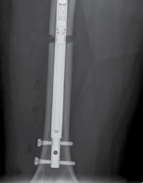

| Surgical techniques have changed in an attempt to minimise these complications. The use of intramedullary implants reduces fixator time and provides regenerate stability. Lengthening over a nail or lengthening followed by nailing still incorporates the use of an external fixator. The development of intramedullary lengthening nails eliminates the need for the external fixator. The initial designs utilised a ratchet mechanism that required rotation of the limb and bone segments to lengthen. A change in design was made where transcutaneous electrical energy drove a motor to improve control in lengthening. The latest and most popular implant is the Precice Intramedullary Lengthening Sysytem (NuVasive Inc., California). This is a magnet-operated telescopic internal lengthening device with an outer casing of titanium alloy (Ti-6Al-4V). A cylindrical rare earth magnet is connected to a gear box and screw shaft assembly within the nail. Two rotating rare earth magnets in an external remote controller (ERC) | |||

| Figure 15.15 Growth arrest in a 12-year-old child. are held over the magnet within the nail, resulting in rotation of the implant magnet which can either lengthen or shorten the nail with sub-millimeter accuracy. Early results are favourable confirming faster regenerate healing times, less complications, better cosmetic results and more favourable patient outcomes compared to lengthening using an external fixator (Figures 15.14–15.17). | |||

Figure 15.16 Completion of lengthening (8 cm).

6 weeks post lengthening 3 months post lengthening

Figure 15.17 Consolidation (8 cm).